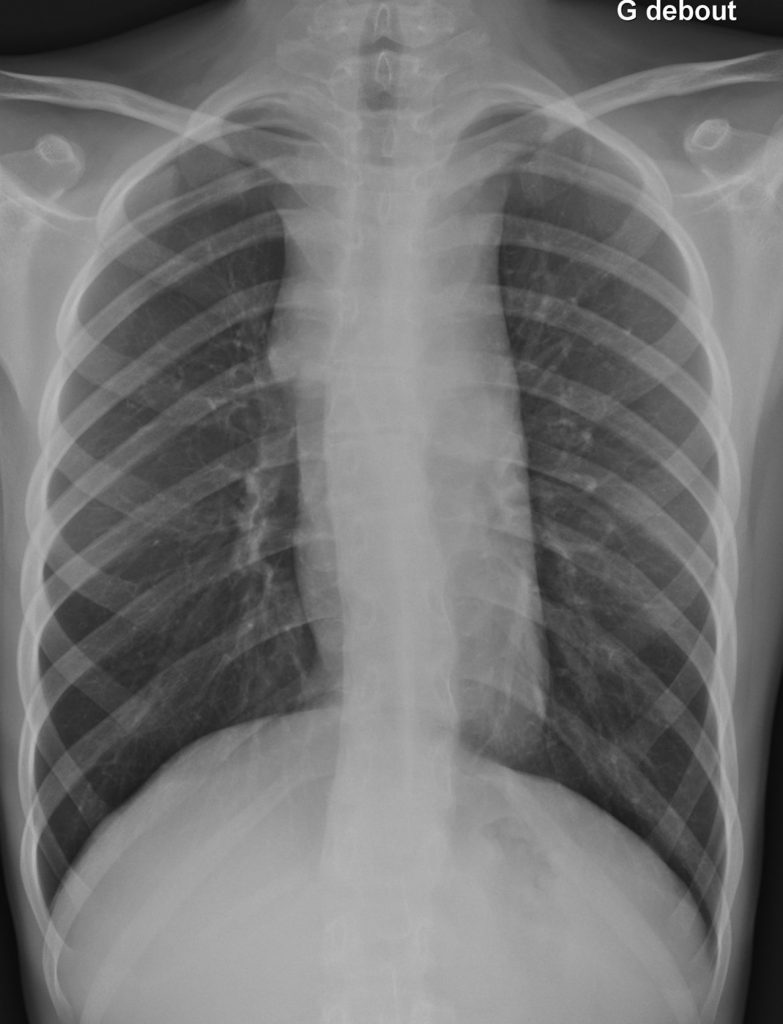

La radiographie pulmonaire est réalisée au début de la prise en charge pour rechercher une atteinte médiastinale éventuelle (le rapport médiastino-thoracique est un facteur pronostique dans la maladie de Hodgkin) (figure 94.1).

Fig. 94.1. Radiographie thoracique de face ; lymphome de Hodgkin.

Élargissement du médiastin supérieur avec aspect en « cheminée ».

Source : CERF, CNEBMN, 2022.